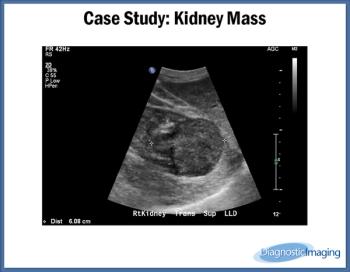

Case History: 90-year-old male had a mass on his right kidney seen on previous ultrasound that was being followed for growth.